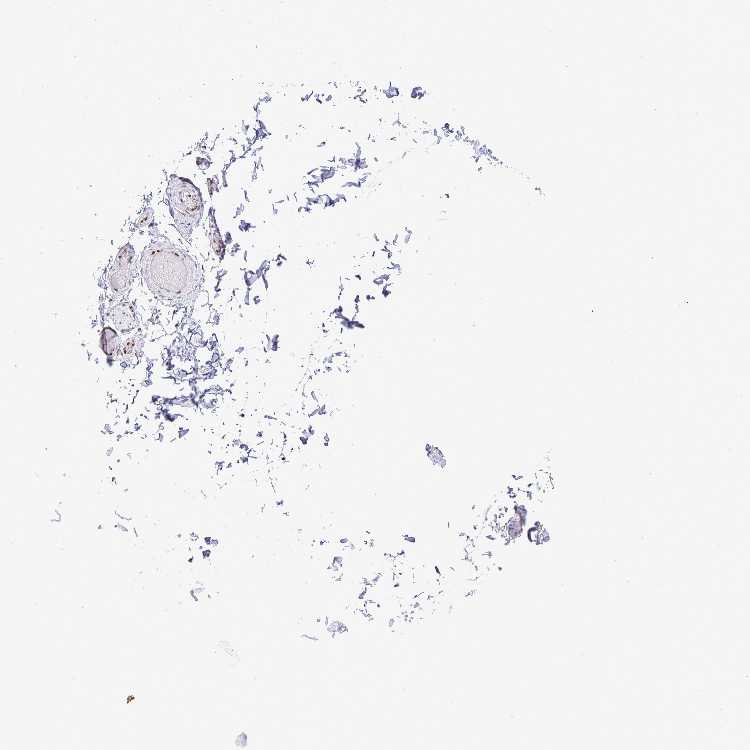

ADIPOSE TISSUE - Antibody stainingi

Antibody staining in the annotated cell types in the current human tissue is reported as not detected, low, medium, or high, based on conventional immunohistochemistry profiling in selected tissues. This score is based on the combination of the staining intensity and fraction of stained cells.

Each image is clickable and will lead to virtual microscopy that enables deeper exploration of all samples and also displays staining intensity scores, fraction scores and subcellular localization as well as patient and tissue information for each sample.

Antibody HPA003506Antibody HPA053314Antibody CAB037206

Adipocytes MediumNot detectedMedium